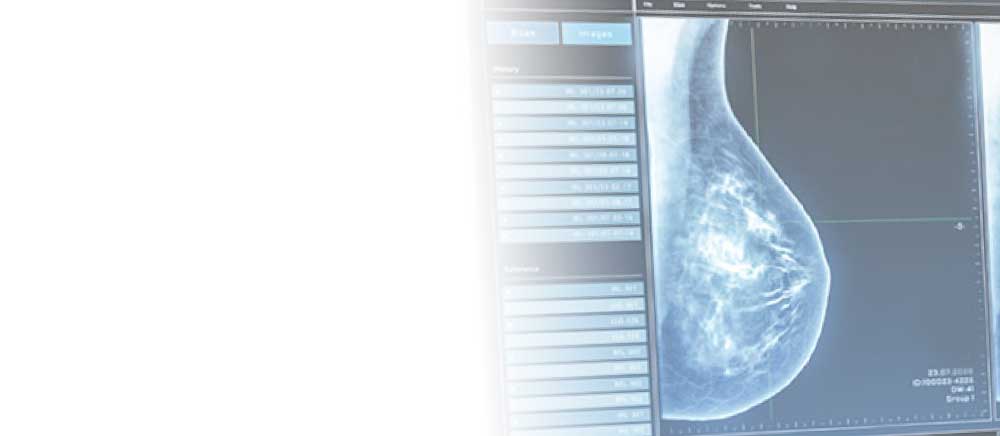

In unserer Praxis informieren wir Sie über die verschiedenen Möglichkeiten der Früherkennung, einschließlich Mammographie und Ultraschalluntersuchungen.